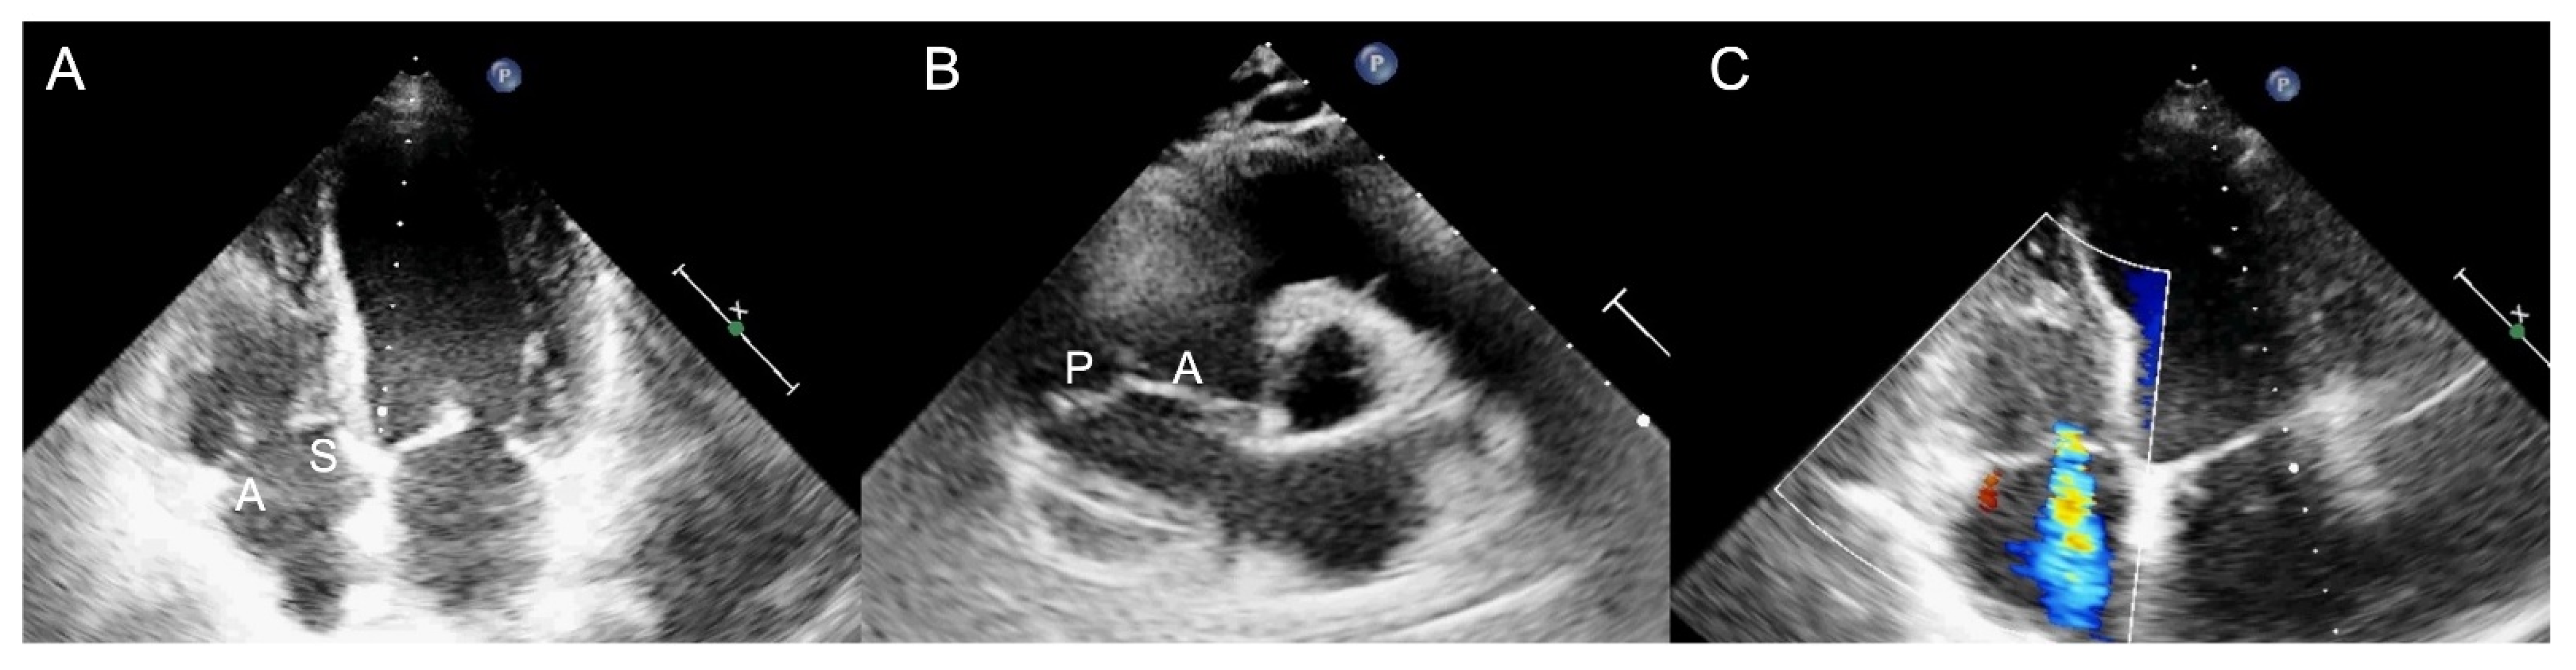

2.1. Two-Dimensional and Three-Dimensional Transthoracic and Transesophageal Echocardiography

3.1. Two-Dimensional and Three-Dimensional Transesophageal Echocardiography

- Ro, R.; Tang, G.H.L.; Seetharam, K.; Khera, S.; Sharma, S.K.; Kini, A.S.; Lerakis, S. Echocardiographic Imaging for Transcatheter Tricuspid Edge-to-Edge Repair. J. Am. Heart Assoc. 2020, 9, e015682. [Google Scholar] [CrossRef] [PubMed]

- Ancona, F.; Stella, S.; Taramasso, M.; Marini, C.; Latib, A.; Denti, P.; Grigioni, F.; Enriquez-Sarano, M.; Alfieri, O.; Colombo, A.; et al. Multimodality imaging of the tricuspid valve with implication for percutaneous repair approaches. Heart 2017, 103, 1073–1081. [Google Scholar] [CrossRef] [PubMed]

- Agricola, E.; Ancona, F.; Stella, S.; Rosa, I.; Marini, C.; Spartera, M.; Denti, P.; Margonato, A.; Hahn, R.T.; Alfieri, O.; et al. Use of Echocardiography for Guiding Percutaneous Tricuspid Valve Procedures. JACC Cardiovasc. Imaging 2017, 10, 1194–1198. [Google Scholar] [CrossRef]